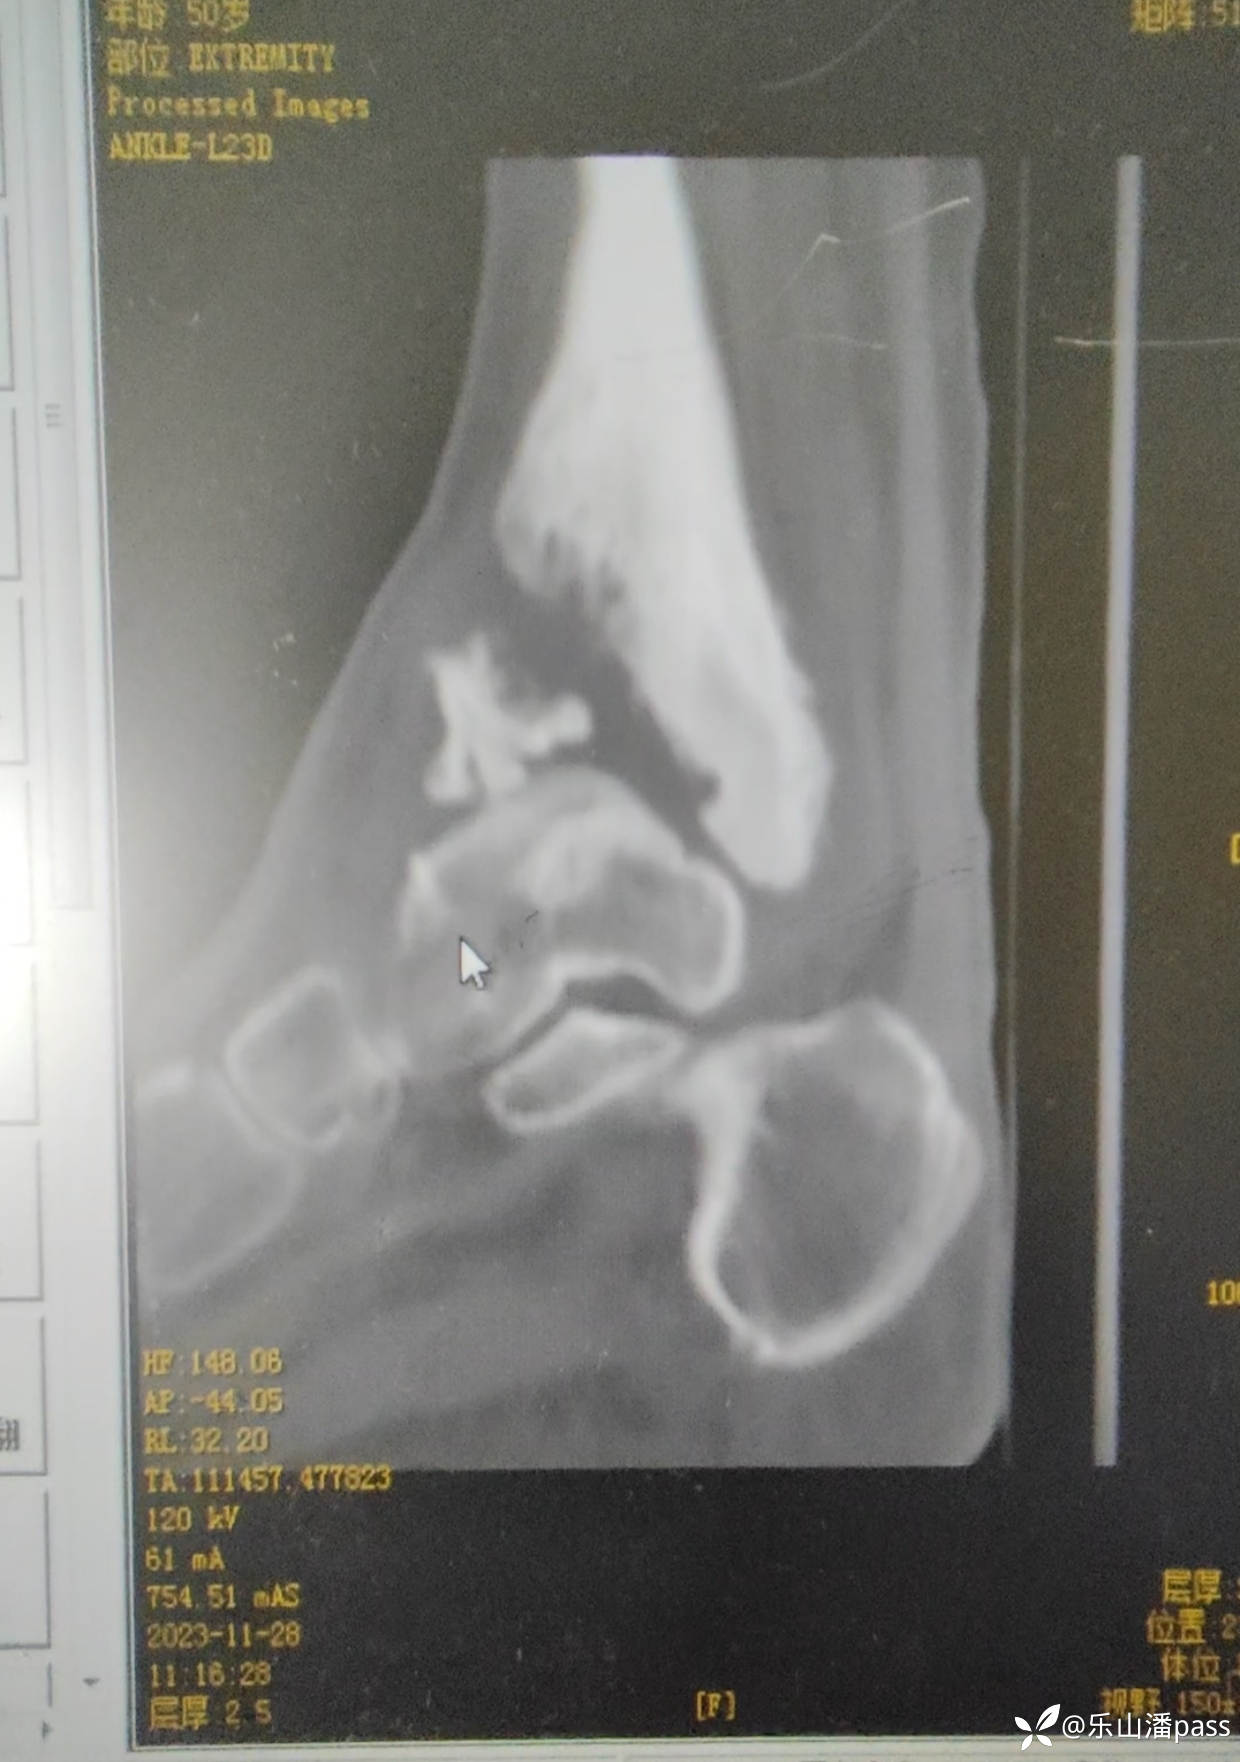

结果,现患者疼痛,来我院检查

img

瞬间傻眼了!